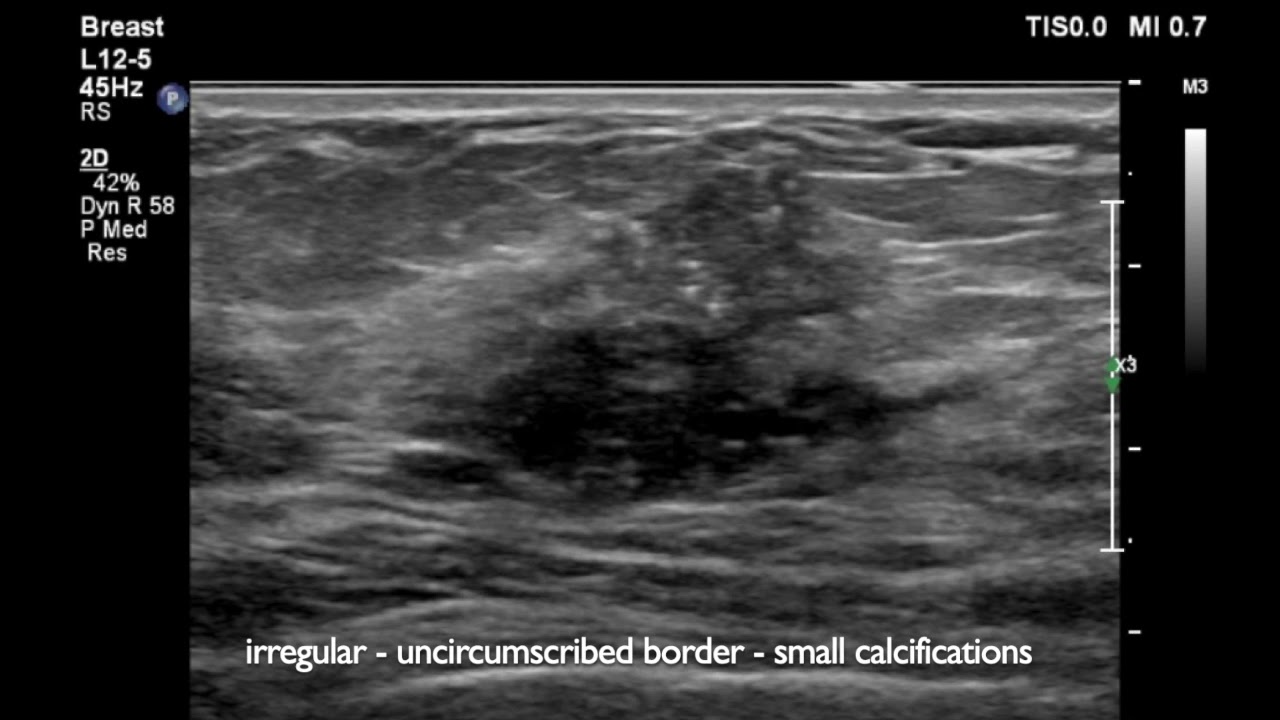

Что может показать УЗИ молочных желез

Ультразвуковое исследование должен проводить опытный специалист, способный отличить структуру, эхогенность, обозначить контуры и форму новообразования, установить его природу и вид. Что показывает УЗИ молочных желез:

- доброкачественное или злокачественное образование